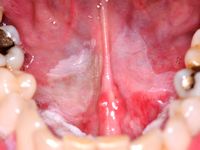

Orale leukoplakie is een witte verkleuring en verandering van het mondslijmvlies. Het komt vaak voor (bij circa 13% van de bevolking kunnen witte verkleuringen worden aangetroffen). Leukoplakie is een beschrijvende diagnose, het histologisch beeld van leukoplakie kan variëren van hyperkeratose met of zonder epitheeldysplasie, via carcinoma in situ en micro-invasief carcinoom tot invasief carcinoom. Klinisch worden er 2 varianten onderscheiden: homogene en niet-homogene leukoplakie. Homogene leukoplakie is een egaal witte verkleuring met een vlak, dun en glad oppervlak. Niet-homogene leukoplakie is een witte of witrode afwijking die irregulair vlak, nodulair of exofytisch kan zijn. Het homogene type is vaak asymptomatisch, terwijl het niet-homogene type gepaard kan gaan met pijn of hinder. Orale leukoplakie kan overgaan in een carcinoom van de mondholte; 17-35% van de carcinomen ontstaan uit preëxistente afwijkingen, vaak leukoplakie. Leukoplakie komt ook voor op andere slijmvliezen (leukoplakie van de penis of de vulva).

Leukoplakie kan worden veroorzaakt door externe factoren zoals roken, mechanische irritatie, candida. In dat geval kan het verdwijnen door die factoren weg te nemen. Indien het na 2-4 weken niet is verdwenen dan gaat het om echte leukoplakie, en is er kans op epitheeldysplasie: het advies is om een biopt af te nemen.

De mate van dysplasie wordt onderverdeeld in gering, matig en ernstig. Er is een direct verband tussen de mate van dysplasie en de kans op maligne ontaarding. De kans op maligne ontaarding binnen 5 jaar is ongeveer 5%. Het ontstaat vooral in niet-homogene leukoplakie.

Risicofactoren voor het ontstaan van leukoplakie zijn roken, alcoholgebruik, Candida infectie, HPV infectie, deficiënte voeding (vooral tekort aan vitamine A, B12, C, beta-caroteen, foliumzuur). Leukoplakie ontstaat meestal vanaf 30 jaar, de meesten zijn ouder dan 50 jaar. De kans op maligne ontaarding is verhoogd bij aanwezigheid van één van de volgende kenmerken: epitheeldysplasie in het biopt; niet-homogene type; vrouwelijk geslacht; langer bestaande leukoplakie; leukoplakie bij niet-rokend persoon; locatie in de mondbodem of op de tong; aanwezigheid van C. albicans.